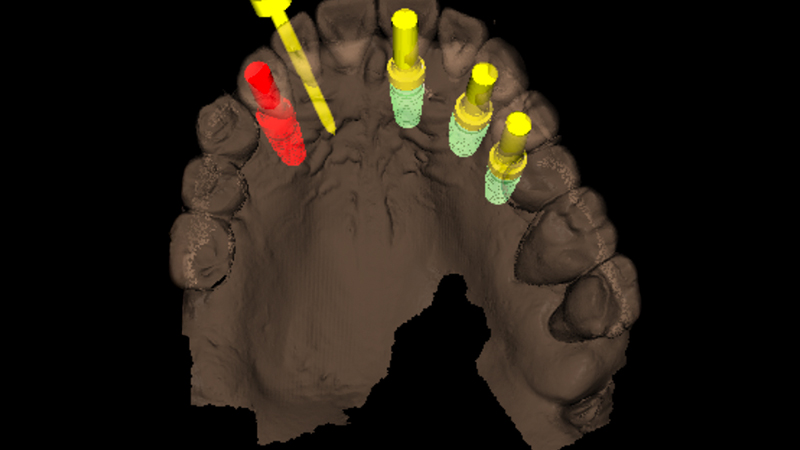

Si è proceduto quindi a pianificare mediante il software R2Gate® la posizione delle fixtures impiantati nei siti che sono stati ritenuti maggiormente favorevoli per poter garantire una stabilità primaria adeguata. Tale procedura è stata semplificata dall’analisi suggerita dal tool “Digital Eye” che ha inoltre suggerito la corretta sequenza di frese da utilizzare per ciascun impianto (Figs. 3, 4, 5)

Pianificazione chirurgica mediante R2Gate

Fig. 3 - Pianificazione chirurgica mediante R2Gate®

Pianificazione chirurgica associata a Digital Eye

Fig. 4 - Pianificazione chirurgica associata a Digital Eye, sequenza di frese individualizzata per ciascun sito implantare